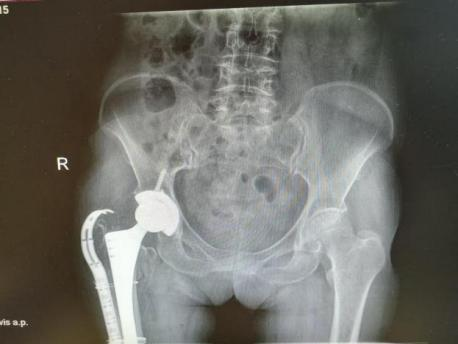

2025年11月1日,由遵义市医学会手外科分会主办、遵义市第二城市医疗集团(贵州航天医院)承办的遵义市医学会手外科分会学术交流会暨贵州省继续医学教育项目《急诊手外伤治疗临床研究新进展专题研讨班》在贵州航天医院成功举办,汇聚了遵义市手外科领域专家及基层医疗骨干,通过专题研讨与临床经验分享,共探急诊手外伤诊疗新进展。 会议特邀遵义市医学会手外科分会主任委员金文虎教授,遵义市医学会手外科分会副主任委员张子阳教授,遵义市医学会手外科分会常务委员杨绍浦教授,贵州航天医院陈明勇教授、赵兴东教授等遵义市手外伤专家进行交流分享;贵州航天医院党委委员、副院长彭亮参加会议并致辞,贵州航天医院骨科医务人员,遵义市第二城市医疗集团成员单位及红花岗区、绥阳县、桐梓县等区县医疗机构手外伤骨干参与。 贵州航天医院党委委员、副院长彭亮致辞 学术交流 本次学术交流以“急诊手外伤治疗临床研究新进展”为主题,通过理论授课与临床案例结合,共同探讨急诊手外伤临床诊疗全链条诊疗策略、关键技术、临床研究新进展,促进规范化诊疗技术向基层下沉,助力提升区域手外伤应急处置与修复能力。 贵州航天医院赵兴东教授分享《急诊手外伤的诊断与治疗原则》 贵州航天医院陈明勇教授分享《开放性骨折的治疗原则》 贵州航天医院张军教授分享《甲沟炎Winograd手术的临床应用》 贵州航天医院赵兴东教授分享《手部常见的皮肤缺损及治疗原则》 贵州航天医院张艳金教授分享《开放性骨折的清创术》 贵州航天医院冷家雄教授分享《下肢创面修复的常用皮瓣之股前外侧皮瓣》 贵州航天医院邬夏荣教授分享《踝关节慢性不稳的诊治》 贵州航天医院卢懿明教授分享《掌骨骨折》 贵州航天医院张艳金教授分享《手部肌腱的解剖与修复方法》 本次研讨班为遵义市手外科领域医务人员提供了深度交流契机,强化了医疗机构间的协作网络,进一步推动学科创新与临床实践融合,为健康遵义建设注入新动能。 贵州航天医院骨科专家简介 陈明勇 骨一科主任,副主任医师 临床擅长:从事创伤骨科工作约20年,对骨缺损、骨不连、骨肿瘤、肢体畸形等的肢体矫形重建及功能重建,慢性化脓性骨髓炎的根治治疗、糖尿病足的保肢治疗、快速康复理念(ERAS)下的老年骨折的诊治,四肢复杂骨折的诊治,四肢骨折等微创手术治疗具有丰富的临床经验。 2004年毕业于遵义医学院临床专业,曾在中国人民解放军总医院、广西医科大学第一附属医院、上海第六人民医院骨科进修。中国中西医结合学会骨伤科专业委员会横向骨搬移治疗糖尿病足及微血管网再生学组首届委员,遵义市医学会创伤分会常务委员。 瞿 晖 骨科党支部书记,骨二科主任,副主任医师 临床擅长:对骨科的常见病、关节外科、脊柱外科及运动医学疾病的诊治具有丰富的临床经验,熟练掌握骨科手术操作技术。 毕业于遵义医学院临床医学系,2005年前往广州中山大学第一附院骨显微医学部进修学习,2011年前往成都华西医院进修学习,并多次在省内外学习骨科相关知识,是中华医学会骨科分会会员。 赵小锋 中共党员,骨二科副主任,副主任医师 临床擅长:从事骨科临床工作11年,对骨科常见病、多发病诊疗有较为丰富的临床经验,擅长脊柱相关疾病诊断及治疗,尤其是颈、腰、腿疼痛疾病诊断及治疗,擅长胸腰椎骨折微创经皮穿刺内固定术、经皮穿刺椎体成形术、经皮穿刺脊柱内镜下腰椎间盘摘除术、单纯开创腰椎间盘摘除术、腰椎滑脱复位椎间植骨椎融合内固定术、腰椎管狭窄减压融合内固定术及人工髋、膝关节置换术等。 2012年毕业于遵义医学院外科学专业硕士研究生,2019年参加“遵义市115医学人才精英计划”于上海交通大学第一附属医院培训学习,2023年于北京大学第三人民医院脊柱外科进修学习,曾获得遵义市优秀医师荣誉称号。 遵义市手外科第一届委员,遵义市医学会创伤分会第一届委员,遵义市医学会创伤分会第二届委员,贵州省康复医学会第三届脊柱脊髓专业会委员,遵义市医学会烧伤与整形外科学分会委员,发表论文5篇,其中国家级核心期刊1篇,SCI论文1篇,主持市级课题1项并结题,参与市级课题2项。 赵兴东 骨科主任医师 临床擅长:擅长骨科的常见病及各种创伤、四肢骨折创伤修复、骨感染、手足疾病的诊治和手足体表畸形的矫形整复,熟练掌握骨科四肢骨病及创伤的手术操作技术,尤其在四肢关节复杂性损伤、手足外伤、组织缺损创面、难治创面的皮瓣修复方面及平足、高弓足矫形方面及四肢慢性疼痛诊治、康复方面具有丰富的临床经验。 硕士研究生,毕业于遵义医学院临床外科系,2015年前往山东省立医院手足外科进修学习;遵义市医学分会创伤分会第一、二届委员,遵义市手外科医学会第二委届员会常务委员;在省级及省级以上期刊发表文章9篇,参编著作2部,参与主持并完成市级课题1项,参与市级课题2项、省级课题1项。 张艳金 中共党员,骨科副主任医师 临床擅长:从事骨外科工作16年,对复合伤、多发伤的救治、四肢骨干骨折、关节周围骨折、骨肿瘤、骨髓炎等诊治具有丰富的临床经验。 中共党员,硕士研究生,2006年本科毕业于山西医科大学第二临床医学院,2011年研究生毕业于北京军区总医院;在“老年COPD患者合并髋部骨折的诊治”国际合作课题组研究两年,在老年髋部骨折的诊治方面具有丰富的经验,并发表论文6篇;主持遵义市级课题1项,承担遵义医科大学的临床教学工作,获得遵义医科大学优秀带教老师荣誉。编撰有《骨科疾病诊疗精粹》一书,开展2项新技术,编撰地方规范《务川自治县创伤骨科常见疾病诊疗规范》一书。 张俊凯 骨科副主任医师 临床擅长:从事骨科临床工作28年,对创伤骨折、骨感染、骨缺损、骨不连等外科诊治,四肢骨折的微创手术治疗,四肢复杂骨折(如关节内粉碎性骨折、多发骨折等)的损伤控制及手术治疗等具有丰富的临床经验。 1995年毕业于遵义医学院临床专业,2009年前往复旦大学附属医院骨科进修1年。 卢懿明 中共党员,骨科副主任医师 临床擅长:从事骨科工作18年,对创伤骨折、四肢骨折的微创手术治疗、四肢复杂骨折(如关节内粉碎性骨折、多发骨折等)的损伤控制及手术治疗,尤其是髋部骨折的PFNA等微创技术,踝关节骨折、膝关节周围骨折的Mipo微创技术等具有丰富的临床经验,开展了4项新技术,发明6项新型专利技术。 2005年毕业于遵义医学院临床专业,2017年,前往南方医科大学第三附属医院骨科进修半年,回院后运用Mipo技术对骨干骨折及干骺端骨折的治疗技术,同时积极开展骨盆骨折、髋臼骨折腹直肌外侧切口的应用;发表了多篇专业论文,经常参与省内外学术交流会授课,获得医院荣誉称号多个。 邬夏荣 骨科副主任医师 临床擅长:从事骨科工作16年,对四肢复杂骨折、骨肿瘤的诊治,尤其是足踝创伤、慢性踝关节损伤、平足症等诊疗具有丰富的临床经验。 2006年毕业于遵义医科大学临床医学专业,曾在陆军军医大学西南医院进修学习,发表多篇骨科学术论文。 余德怀 中共党员,骨科副主任医师 临床擅长:从事骨科工作10余年,对运动医学、骨关节、脊柱外科常见病、多发病的诊治具有丰富的临床经验。 硕士研究生,2011年毕业于遵义医学院临床医学专业,曾前往遵义医科大学附属医院运动医学专业进修学习;是贵州省医学会运动医学分会青年委员,西部关节镜联盟委员;发表多篇骨科学术论文。 冯 乾 骨科副主任医师 临床擅长:从事骨科工作近20年,熟练掌握骨科多发病及常见病的诊治,尤其对脊柱退变性疾病的诊断及治疗具有丰富的临床经验,主要研究脊柱微创相关治疗方式,能熟练开展椎间孔镜及UBE。 曾前往北京大学第三医院进修学习疼痛及椎间孔镜、首都医科大学友谊医院专业进修脊柱内镜;是贵州省康复医学会第三届脊柱脊髓专业委员会委员;发明专利3项、发表脊柱外科专业论文多篇。 贵州航天医院骨科简介 基本情况 贵州航天医院(原3417医院)骨科组建于1968年,前身是以创伤和断肢(断指)再植闻名于世的上海市第六人民医院骨科,中国断肢(断指)再植的奠基者、中科院院士陈仲伟等专家莅临科室指导医疗和教学,并在70年代开展了贵州省首例断肢(断指)再植手术。组建50余年来,诊治患者已逾百万,挽救了无数的伤病员,成为了保障遵义地区人民群众健康的重要支撑。 经过几代人的不懈努力,今天的骨科,已由创伤骨科发展至骨病、骨肿瘤、骨结核等领域,现有脊柱外科、关节外科、四肢创伤、手足外科四个亚专科,成为了集医疗、教学、科研于一体的综合学科,是贵州省临床重点专科、遵义市临床重点专科、遵义市骨科临床医学中心、遵义市基层骨科专科联盟理事长单位。 科室目前开放床位110张,共有医护人员50余人,副高级以上专家18人,硕士研究生15人。拥有一流骨科医疗设备多台,每年不定期选派优秀技术骨干到全国各大知名医学院校进修、学习、参观、交流,并邀请国内、国外知名专家教授来院进行交流、指导,通过不断引进国内外先进的诊疗技术,科室医疗技术水平稳步提升,为广大人民群众提供了优质的医疗服务。 专科特色 骨一科 (一)骨缺损、骨不连的肢体与功能重建 胫骨横向骨搬移技术治疗糖尿病足: (二)慢性骨髓炎的根治治疗 (三)肢体缺血性疾病如糖尿病足、脉管炎的保肢治疗 (四)皮瓣修复 (五)复杂创伤的治疗 (六)老年髋部骨折及小儿骨折快速手术 老年髋部骨折: 骨二科 (一)胸腰椎骨折微创经皮椎弓根螺钉固定术 (二)老年性骨质疏松性患者腰椎滑脱脊柱内固定术(骨水泥螺钉) (三)V形双通道脊柱内镜技术(VBE)腰椎融合术治疗腰椎退行性疾病 (四)老年性骨质疏松性骨折(PVP/PKP)术 (五)人工髋关节置换术 (六)双侧股骨头坏死人工全髋关节置换 (七)右侧全髋置换术后假体周围骨折翻修 (八)人工膝关节置换术 (九)人工膝关节假体松动翻修 (十)关节镜技术 传统手术切口 关节镜技术切口 诊疗范围 骨一科 1.四肢创伤、矫形。 2.手、足踝外科。 骨二科 End